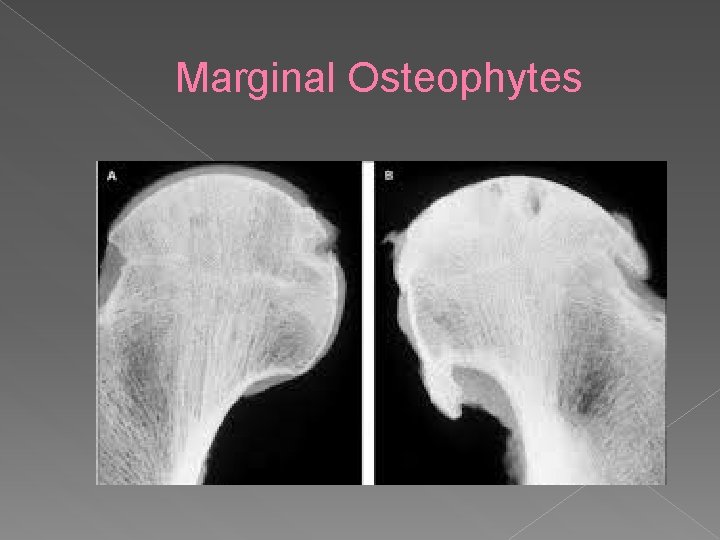

Marginal Osteophytes